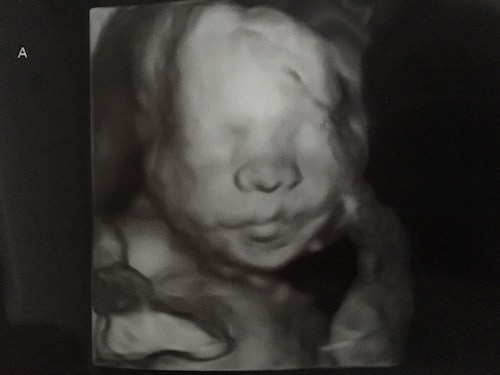

Ultrasound Photos at 22 Weeks Pregnant With Twins